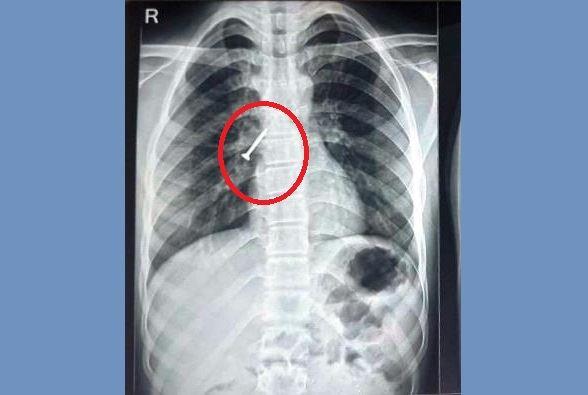

सहायक प्रोफेसर डॉ. महेश माहिच ने बताया कि युवक सुथारी का काम कर रहा था। काम करते समय वह गलती से एक लंबा स्क्रू निगल गया था, जो सीधे उसके दाएं फेफड़े की श्वास नली में जा फंसा। इसके कारण मरीज को लगातार खांसी, छाती में दर्द और बलगम में खून आने की गंभीर समस्या हो गई थी। परिजन 25 अप्रेल को गंभीर हालत में उसे हॉस्पिटल लेकर आए। स्थिति की गंभीरता को देखते हुए चिकित्सकों की टीम ने अगले ही दिन 26 अप्रैल को फ्लेक्सिबल ब्रान्कोस्कोपी तकनीक प्रयोग करते हुए प्रोसीजर संपन्न किया गया और फेफड़े में फंसे स्क्रू को बिना चीरा लगाए श्वास नली के रास्ते बाहर निकाल दिया। udaipur TB Hospital doctors team remove 32mm screw using flexible bronchoscopy technique

आरएनटी मेडिकल कॉलेज के प्रिंसिपल डॉ. राहुल जैन ने बताया कि बड़ी स्थित टीबी एवं चेस्ट अस्पताल द्वारा बिना जनरल एनेस्थीसिया (बेहोशी) और बिना किसी सर्जरी के फ्लेक्सिबल ब्रान्कोस्कोपी के जरिए इस स्क्रू को निकालना चिकित्सकों की उच्च स्तरीय कुशलता को दर्शाता है। आमतौर पर ऐसे मामलों में बड़े ऑपरेशन या रिजिड ब्रान्कोस्कोपी की आवश्यकता होती है, लेकिन हमारी टीम ने मिनिमल इन्वासिव के साथ मरीज को राहत दी है। आरएनटी मेडिकल कॉलेज से संबद्ध अस्पतालों में अब जटिल से जटिल फॉरेन बॉडी रिमूवल की सुविधाएं सुलभ हैं, जो आमजन के लिए राहत की बात है।